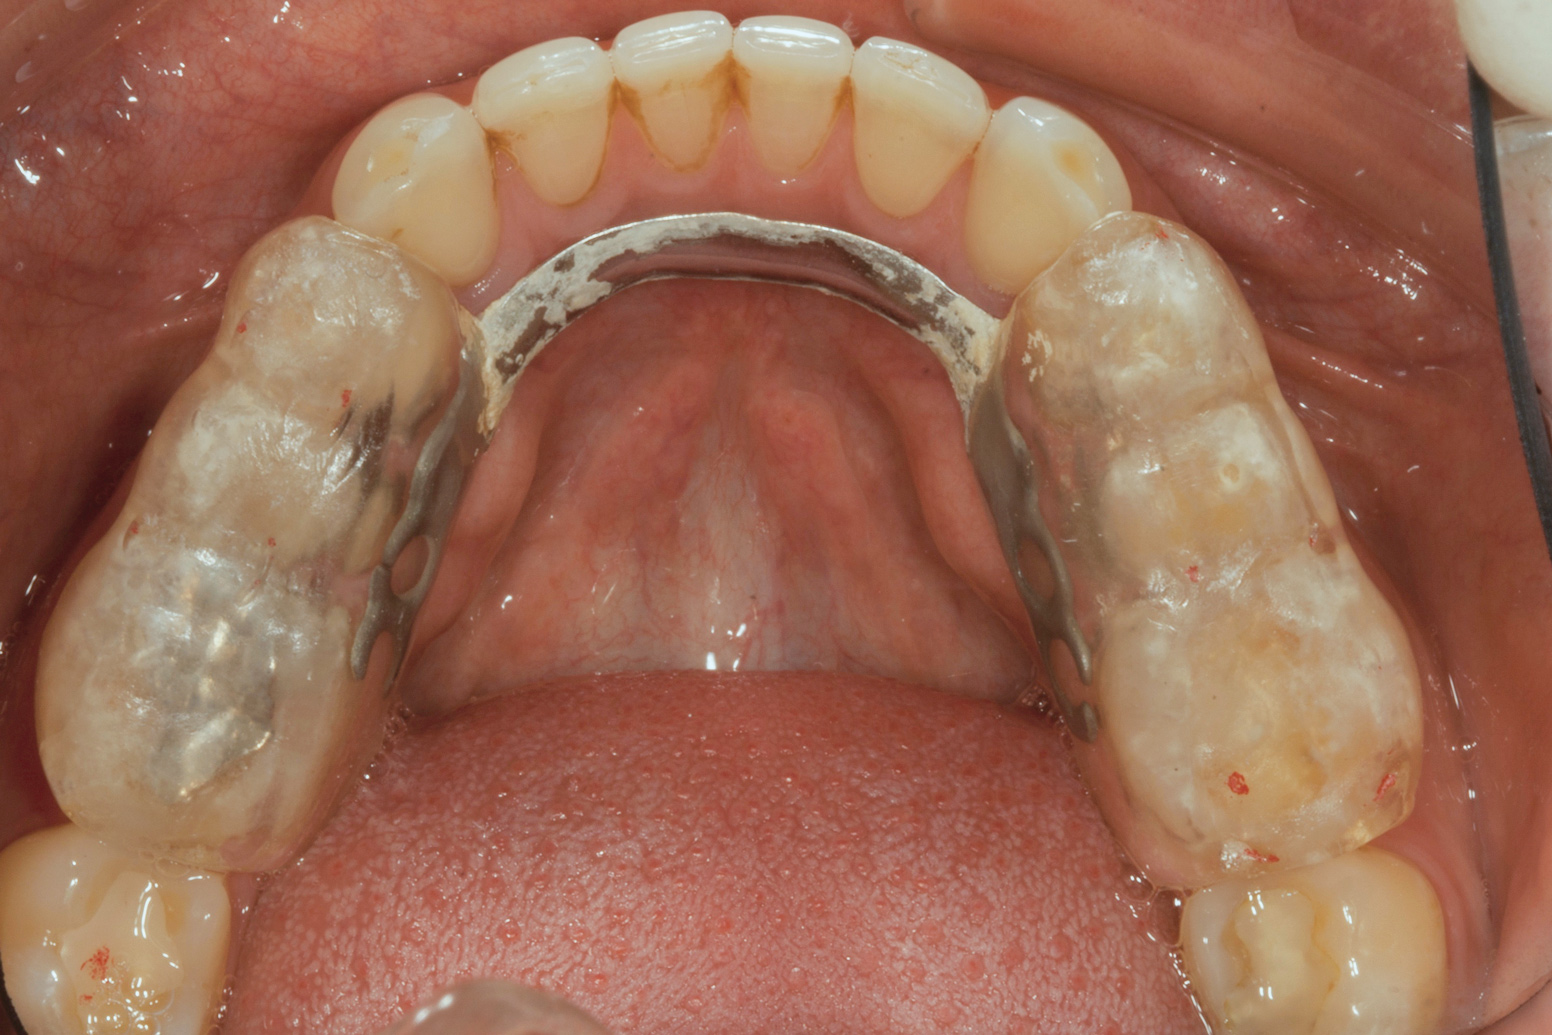

Ultimately, the patient developed joint and muscle symptoms due to his lack of posterior support and sought the help of a specialist. His bite was analyzed, and he was fitted with a dental orthotic that allowed his teeth to touch in centric relation (Figure 3). This was intended to be a temporary measure to stabilize the patient's bite and make him comfortable, but before any permanent treatment could be carried out, he moved abroad and had been living with the device for more than four years before the time of the consultation. He stated that his bite was now very stable with the orthotic, but he was looking for a more permanent solution and also wanted to improve the overall appearance of his smile.

The patient's removable dental orthotic covered the lower bicuspids and first molars. With the orthotic in place, there was shim stock contact on all posterior teeth and on the second molars that were not covered by the appliance. However, there was no incisal overlap and a lack of anterior guidance.11 When the orthotic was removed, solid shim stock contacts were present on the second molars and the right lateral incisor. These contacts were reproduced every time the appliance was removed. The same contacts were found on the patient's mounted models, which confirmed that the joints were in centric relation. Whether the lower second molars had overerupted as a result of wearing the appliance or had already been in this position before the orthotic was fitted could not be established. Apart from these three contacts, no other teeth touched, and there was a 2-mm space between the posterior teeth, making mastication difficult. Interestingly, wear facets were present on the palatal surfaces of the upper central and lateral incisors, indicating that at some point in time, there had been significant overlap of the anterior teeth and a possible constriction of the chewing envelope. Analysis of a cephalometric radiograph showed a class II growth tendency with a reduced mandibular plane angle, which supported the theory that the patient had at one time possessed a class II occlusion.

(3.) Preoperative occlusal view of lower arch with orthotic in place.

Figure 3